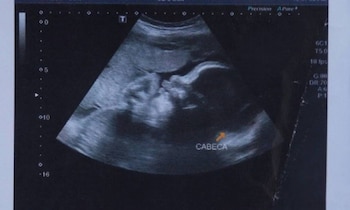

Las autoridades indicaron que la madre de Arthur fue baleada el 30 de junio, en la Favela do Lira. El bebé, aún en el útero, también fue alcanzado. La mujer fue llevada al Hospital Moacyr do Carmo, donde los médicos realizaron una cesárea de emergencia.

Tras su nacimiento fue internado en estado grave en el hospital estatal y respiraba con ayuda mecánica, ya que la bala le golpeó el tórax, le hirió el cráneo, le desgarró una oreja y llegó a atravesar su columna (alcanzó dos vértebras), según informó días atrás la cadena BBC.